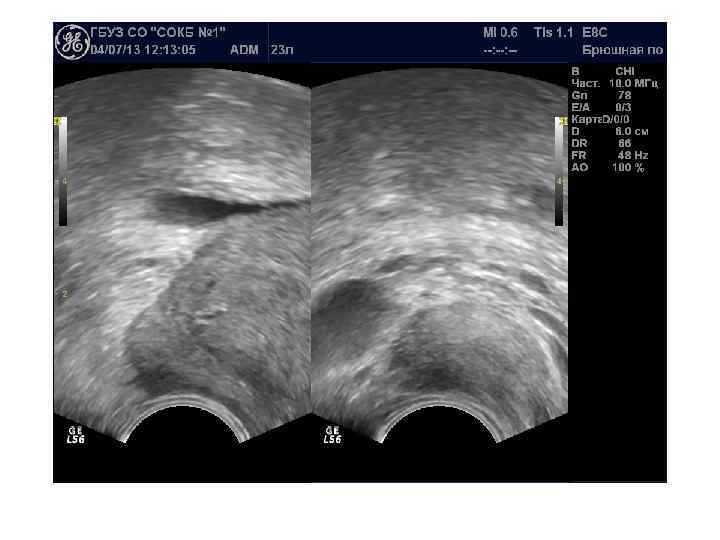

Доступы: трансабдоминальный, трансперинеальный, трансректальный, трансуретральный Трансабдоминальное исследование производится с помощью датчиков 3, 5— 5, 0 МГц и требует наполнения мочевого пузыря. При трансабдоминальном исследовании можно определить размеры и объем предстательной железы, выявить изменения, характерные для ДГПЖ, и определить особенности роста аденоматозных узлов. Не используется для выявления рака простаты. Трансперинеальное (чреспромежностное) исследование простаты: датчик 3, 5— 5, 0 МГц устанавливается на промежность. Исследование проводится при невозможности выполнения трансабдоминального или трансректального исследований. Качество визуализации не лучше чем при трансабдоминальном

Для трансректального исследования (ТРУЗИ) простаты необходим полостной трансректальный датчик 7, 5— 10, 0 МГц. При ТРУЗИ возможно точное определение размеров и объема железы, выявление тонких структурных изменений и особенностей кровоснабжения паренхимы. Исследование позволяет детально оценить состояние железы при ДГПЖ, особенности роста аденоматозных узлов, состояние паренхимы и капсулы. Трансуретральное исследование простаты не имеет существенных преимуществ перед трансректальным при значительно более инвазивной технологии.